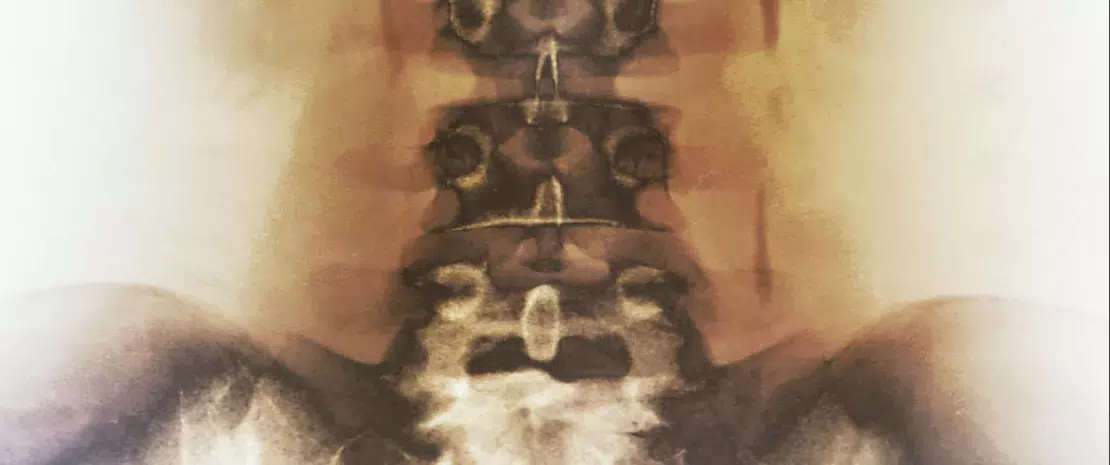

Une équipe italienne a étudié le microbiote intestinal de 52 patients ayant eu au moins deux épisodes symptomatiques de calculs rénaux constitués à plus de 80% de cristaux d’oxalate de calcium (groupe C+), et l’a comparé à celui de 48 témoins sains. Ce type de calcul est identifié dans 70 % des coliques néphrétiques, généralement sans cause primitive retrouvée. Seule l’alimentation (apports de calcium et d’oxalate trop importants) est actuellement incriminée dans la genèse de ces lithiases idiopathiques, souvent récidivantes. L’implication du microbiote intestinal avait déjà été suggérée par une étude mettant en évidence la capacité d’une bactérie intestinale (Oxalobacter formigenes)à dégrader l’oxalate, réduisant ainsi son absorption et son excrétion urinaire.

Genres bactériens impliqués dans l’oxaliurie